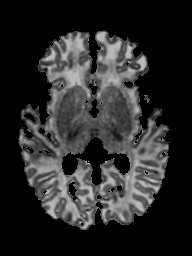

Qualitative Results

In Figure 3, we show two examples from the test set. We show four images per subject: (1) the input with its age that gets encoded into a latent vector, (2) the reconstruction of the input at , (3) the target ground truth from and (4) the prediction at age . Note that for our model, does not necessarily have to be greater than , we can also choose to look back in time to predict what a given brain has looked like in the past. The reconstructions display the input images with some loss of details due to the bottleneck created by the low-dimensional latent space. The predictions generally match the size and the contrast of the target ground truth well, but have trouble predicting the exact shape of the cortical folds. This is, however, a difficult task, as even for monozygotic twins, the folds exhibit individual patterns [25]. On the bottom right, we see an interesting example where the mid-sagittal plane of the input is slightly off the vertical, in contrast to the target ground truth. Interestingly, however, the reconstruction, as well as the prediction, display this slight rotation, which means it must have been encoded in the latent vector.